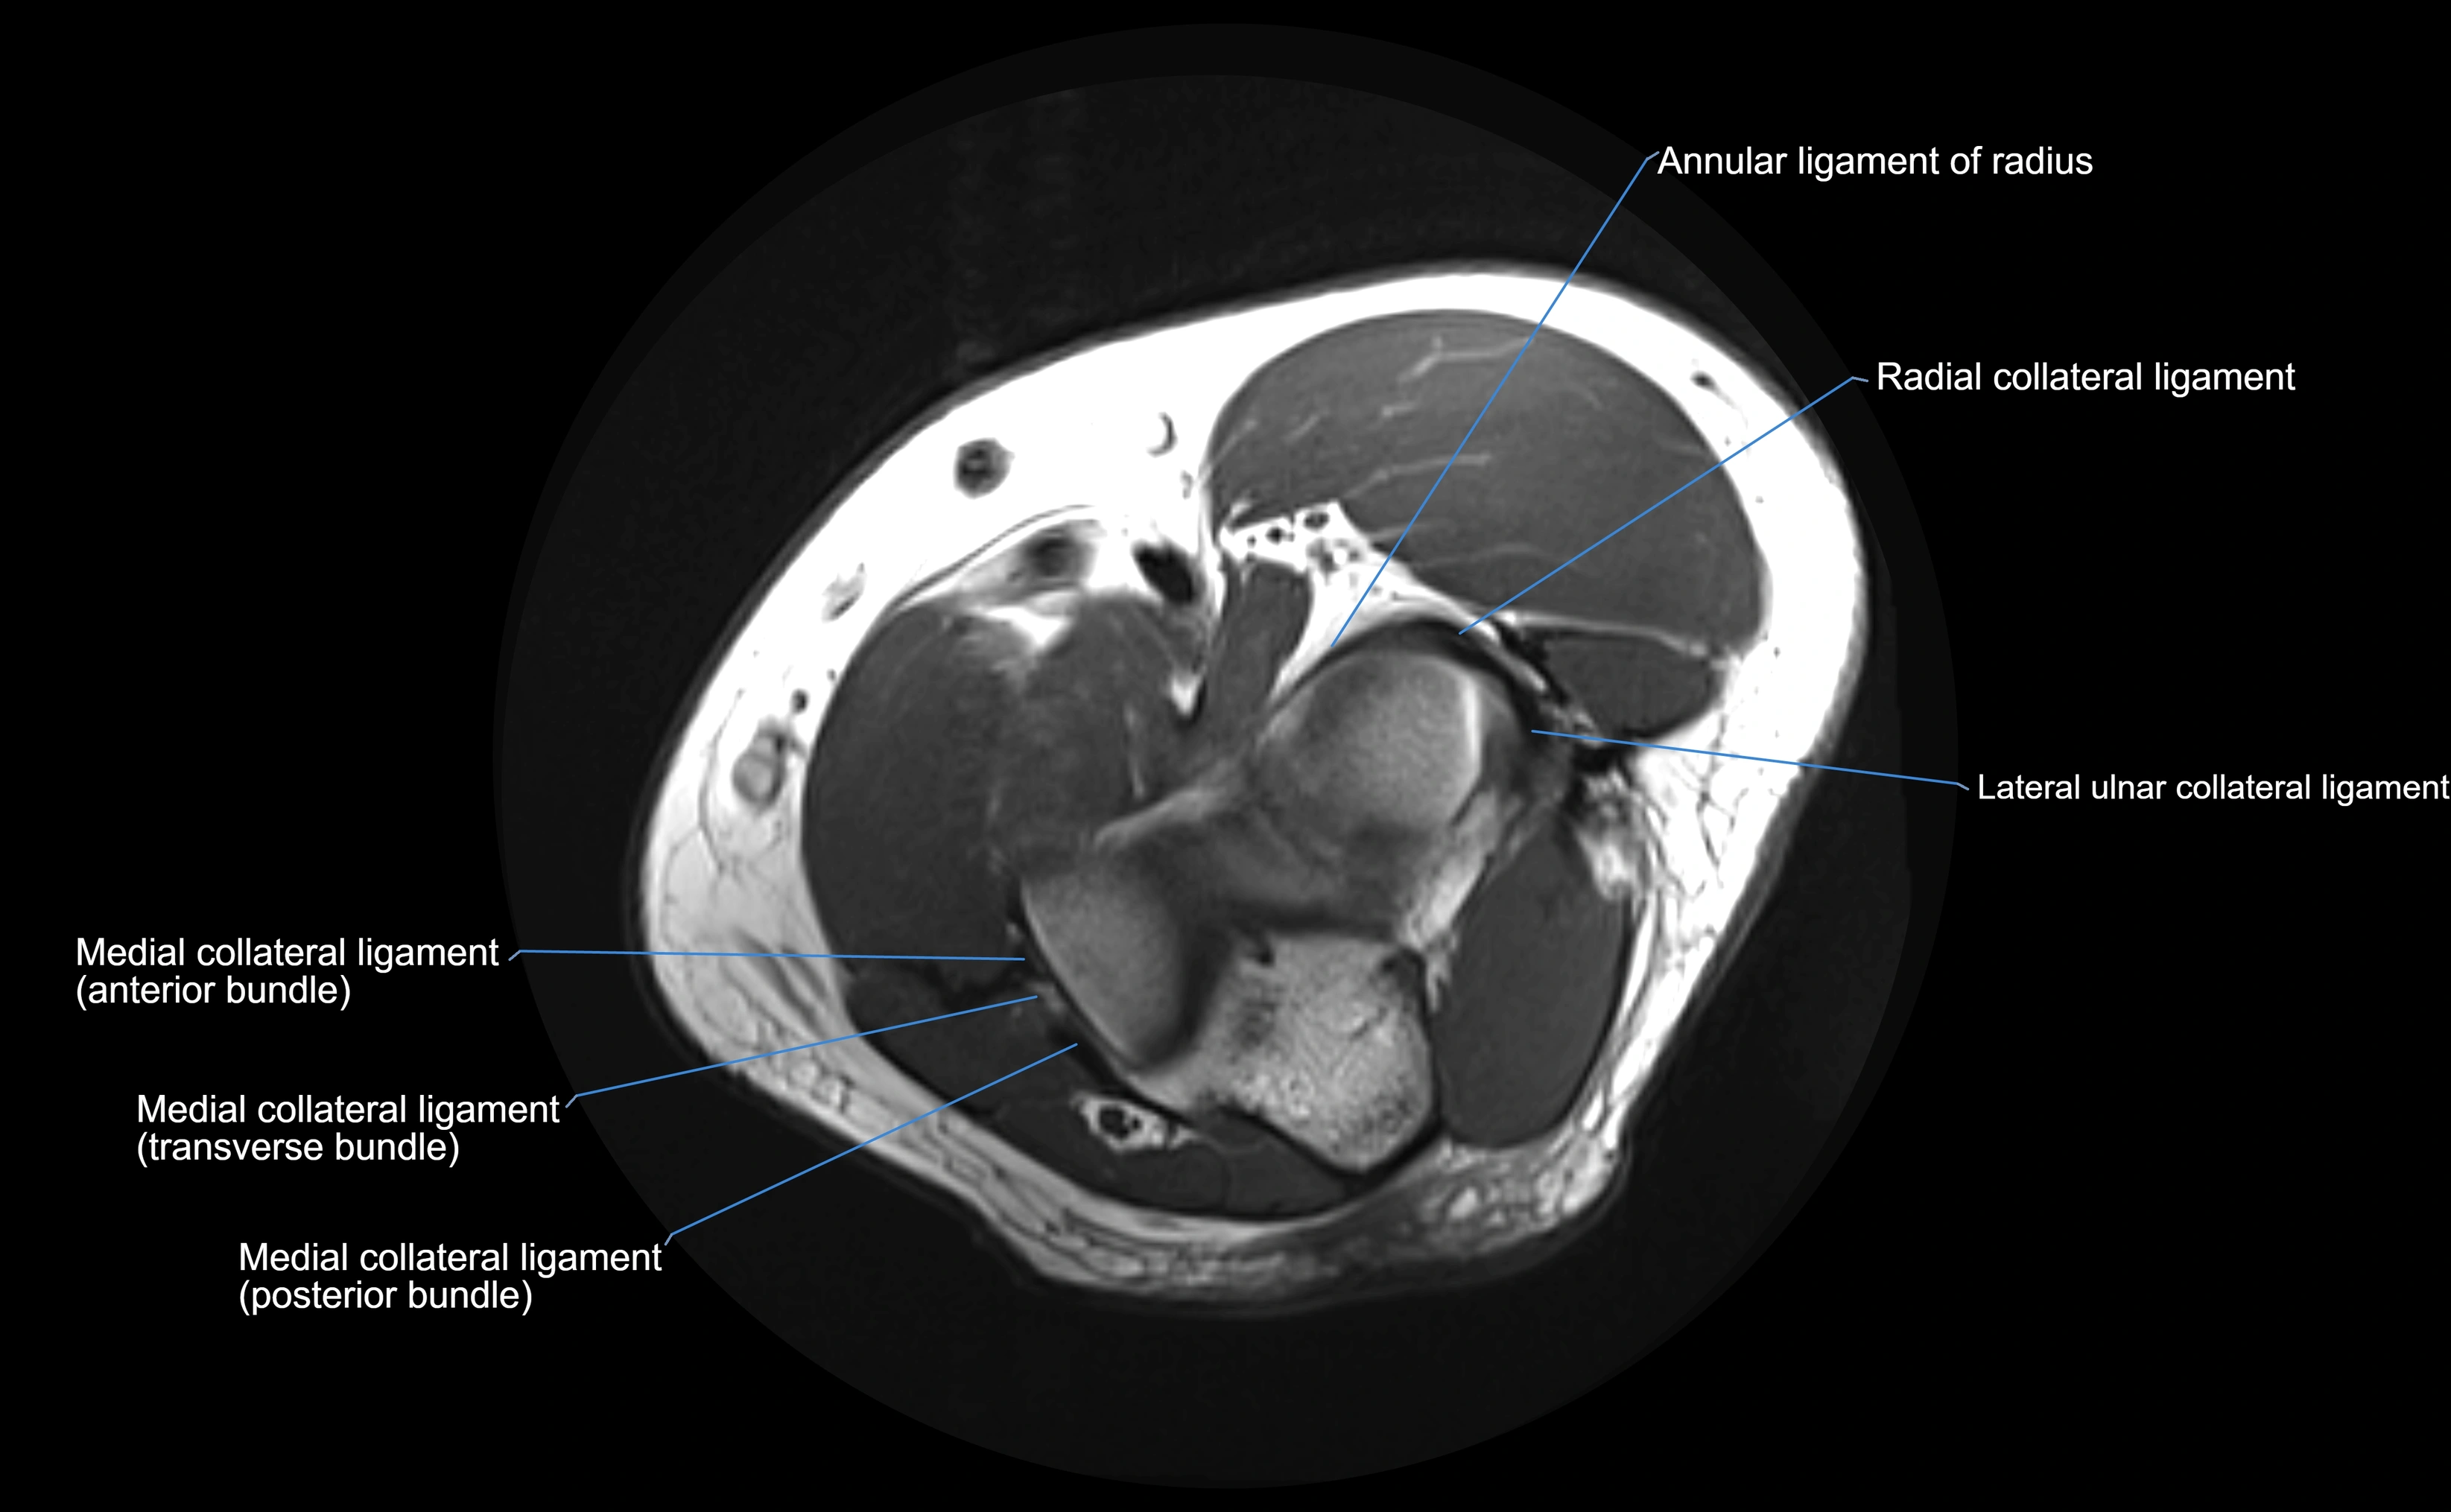

MRI Appearance

T1-weighted images:

• Ligament: low signal intensity (dark), appearing as a continuous band around the radial head.

• Adjacent fat and marrow: bright, creating contrast with the ligament.

• Thickening or disruption indicates injury or fibrosis.

• Joint capsule and synovium seen as thin low-signal lines contiguous with ligament margins.

T2-weighted images:

• Ligament: low signal (dark) with clear delineation from joint fluid.

• Fluid or edema: bright hyperintense, separating or surrounding the ligament in partial tears.

• Complete tear: discontinuity or non-visualization of ligament fibers, often with joint effusion.

MRI Arthrogram Appearance

• Contrast outlines the proximal radioulnar joint and radial head recess.

• Normal ligament appears as a dark ring surrounding the radial head, containing the injected contrast within the joint cavity.

• Partial tear: contrast extends along the ligament or beneath its fibers.

• Complete tear or subluxation: contrast extravasates around the radial head or ulna, indicating discontinuity.

• Detects capsular defects, instability, or synovial invagination with high sensitivity.